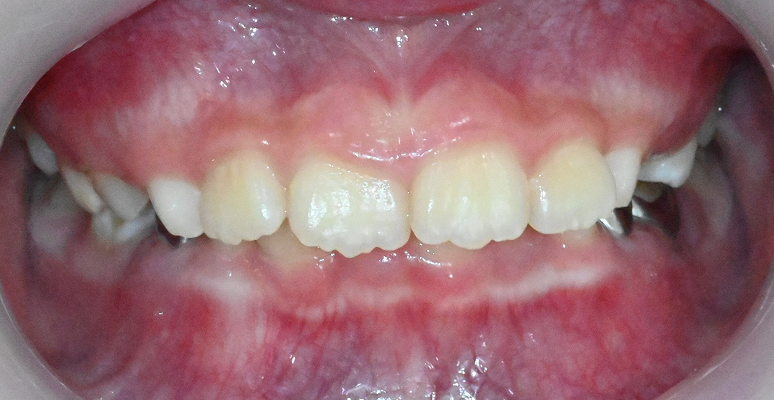

이숲치과 성장기 교정의 특징

연세대 출신 교정과 전문의가

직접 진단 및 관리

인비절라인 퍼스트 및

디지털 교정 시스템 완비

교정 중 성장 모니터링으로

얼굴 균형까지 함께 관리

• A

일반적으로 만 7세 전후, 영구치가 앞니와 어금니 일부 맹출할 때부터 가능하고, 빠르면 만5~6세 정도 유치열기 부터 가능합니다. 이 시기에 교정과 전문의의 검진을 받아, 성장 방향을 미리 점검하는 것이 중요합니다.